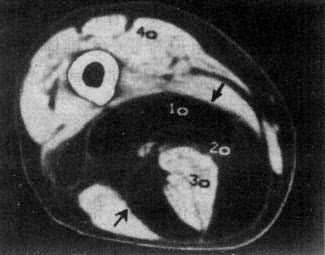

软组织肿瘤的密度一般低于正常肌肉,增强扫描可增加病变和正常肌肉的密度差,多数良性肿瘤边界清楚或有包膜且质地均匀,但定性诊断有一定限度。脂肪瘤因有典型的脂肪密度,表现具有特征性(图2-2-1)。海绵状血管瘤于肿块内可见小圆形静脉石,且在造影增强扫描后,肿瘤明显强化,具有一定的特点。

图2-2-1 大腿脂肪瘤

右大腿中1/3后内侧低密度肿块,境界清楚,CT值-100Hu